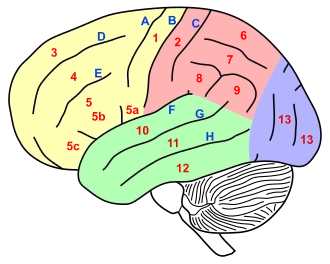

5. Gyrus frontalis inferior

5a/b Broca-Areal

10. Gyrus temporalis superior

11. Gyrus temporalis medius

G Sulcus temporalis superior.

Das Wernicke-Zentrum befindet sich in etwa an der Stelle des Buchstabens „G“.